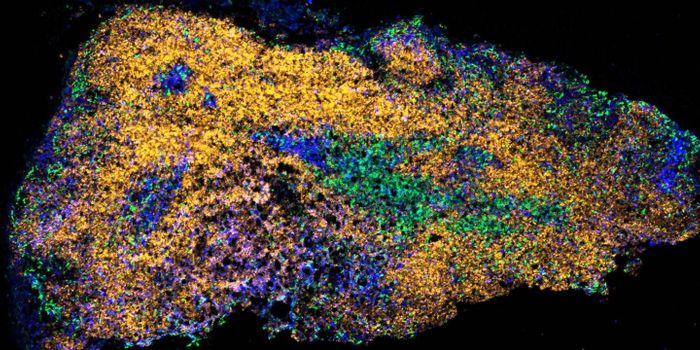

NOV 13, 2018ImmunologyPancreatic Cancer is a devastating disease. Fifty-five thousand new patients were diagnosed this year in the United Stat ...